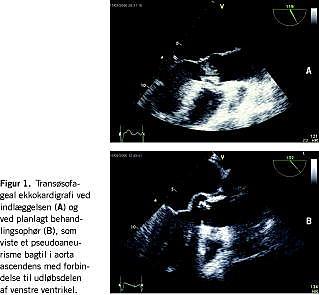

Sygehistorier

I. En 61-årig mand blev opereret for aortastenose med indsættelse af en mekanisk aortaklapprotese. Et halvt år efter operationen blev patienten indlagt via ambulatoriet pga. subfebrillia, nattesved og åndenød. En TEE viste tegn på endokarditis i klapprotesen med løshed af protesen, randlækage og en flagrende excrescens, men ingen tegn på pseudoaneurisme (Figur 1A). Bloddyrkninger viste vækst af Staphyloccccus albus, og der blev påbegyndt antibiotisk behandling med rifampicin og vancomycin. Herefter blev patienten overflyttet til en thoraxkirugisk afdeling, hvor man udskiftede klapprotesen med en homograft. Patienten fortsatte den antibiotiske behandling og blev afebril med stationært leucocyttal ved øvre normale grænse og C-reaktivt protein (CRP) omkring 20. Efter godt to ugers antibiotisk behandling fik patienten subfebrilia med eosinofili, som blev behandlet med antihistamin. Pga. fortsat subfebrillia og stigende eosinofili skiftedes vancomycin til clindamycin, hvorefter patienten blev afebril og leucocyttallet normaliseredes. Efter endnu to ugers antibiotisk behandling, hvor patienten var helt velbefindende, blev der foretaget TEE forud for det planlagte ophør med antibiotika. TEE viste et pseudoaneurisme bagtil i aorta ascendens med forbindelse til udløbsdelen af venstre ventrikel (Figur 1B). Ved TTE en uge forinden havde man ikke påvist forandringer omkring protesen. Patienten fik foretaget en operativ lukning af pseudoaneurismet uden udskiftning af homograften. Forløbet var herefter ukompliceret bortset fra atrieflimren.